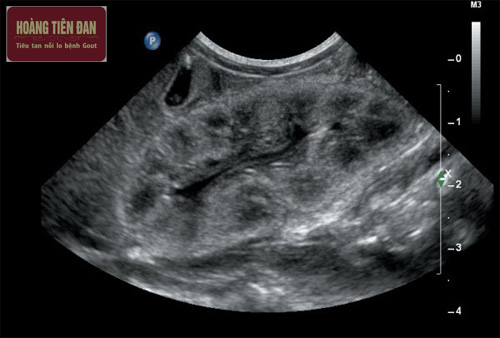

+ Siêu âm

Xét nghiệm này sẽ giúp tìm ra những bất thường của thận và các vật thể gây nghẽn dòng nước tiểu. Tuy nhiên xét nghiệm này sử dụng sóng âm thanh để có hình ảnh của thận.

Siêu âm là một xét nghiệm thường được chỉ định để xác định bất thường ở thận